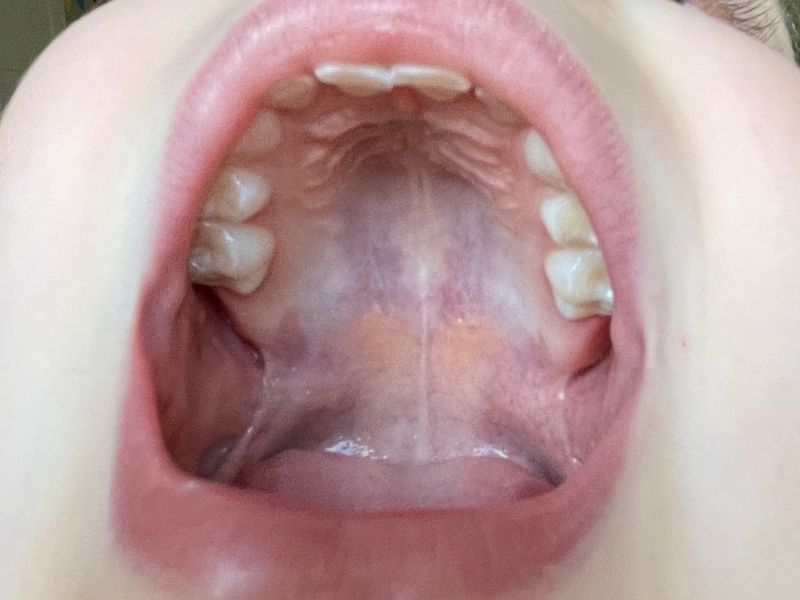

Von einer pathologischen Zungenruhelage wird gesprochen, wenn sich die Zunge unten im Mund befindet: